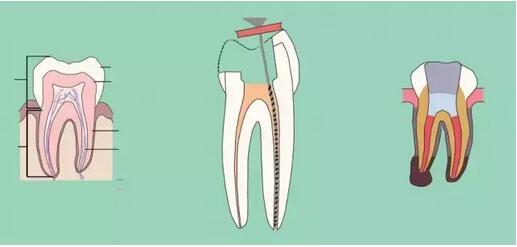

七、根管充填

充填時(shí)機(jī),無(wú)自覺(jué)癥狀,無(wú)明顯叩疼,根管內(nèi)無(wú)異味,無(wú)滲出,無(wú)急性尖周炎癥狀即可充填,不必等到所有癥狀消失,反復(fù)的封藥容易對(duì)尖周造成大大刺激。

充填的質(zhì)控標(biāo)準(zhǔn):

a、充填物距根尖小于等于2mm;

b、充填致密,連續(xù),錐度合適;

c、充填完畢燙牙膠尖根管口下2~3mm,小號(hào)充填器冷加壓;

d、對(duì)于欠充患者需重新預(yù)備充填,而超充原則上不建議重做,隨訪,必要時(shí)根尖手術(shù)治療。目前研究表明,在其他因素相同的前提下,超充的預(yù)后差于欠充。